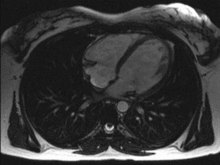

الرنين المغناطيسي

من الطرق الحديثة في فحص القلب التصوير الطبقي باستخدام الرنين المغناطيسي، وهي ما زالت قيد التطوير، وتمكننا من فحص الوظيفة القلبية وفحص التروية الدموية للقلب بنفس الوقت، كما تعطي معلومات قيمة أخرى حول التركيب النسيجي للعضلة القلبية.

ما زالت هذه الطريقة قيد البحث، إذ أن أجهزة الرنين المغناطيسي نفسها يتم تطويرها بسرعة كبيرة، إلا أنها تعاني من ارتفاع السعر، وكون الفحص بالرنين المغناطيسي يحتاج تجهيزات أعقد بكثير من الطريقة المثلى وهي صدى القلب.